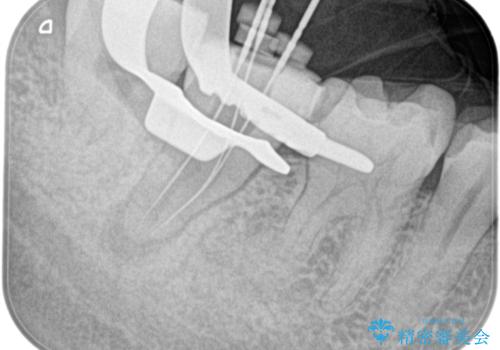

- 定期検診にて膿の出口を見つけたことを主訴に来院されました。

検査の結果、診断を歯髄壊死、症候性根尖性歯周炎とし抜髄を行っております。

根管充填はCWCTにて行なっています。